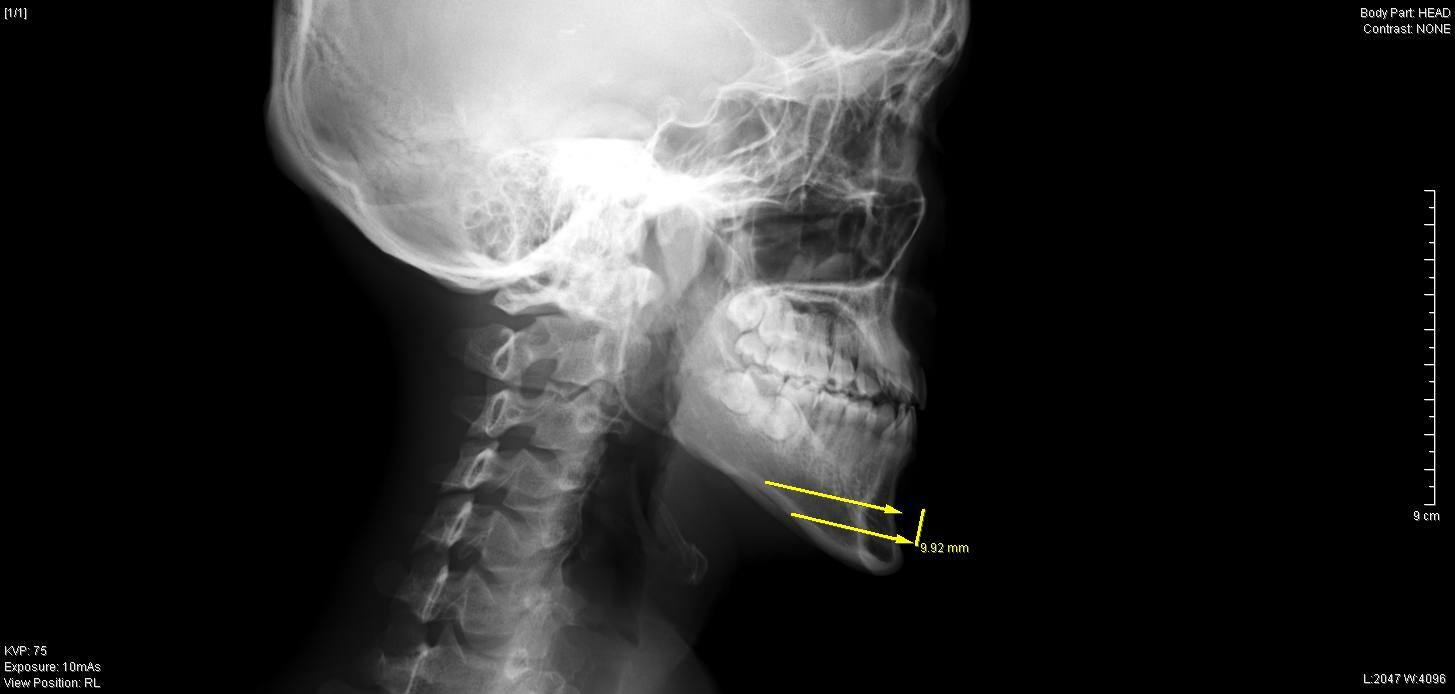

今回の症例は、30代の男性です。

顎を短くしたいというご希望で来院されましたが、

『おとがい』が後退しており、

通常の下顎骨切りを行うとさらに顎が後退したようになる為、

中抜き法を選択しました。

今回の症例では、最大9mm幅で下顎骨を中抜きし、

おとがい先端を約4mm前進させて

チタンスクリュー、プレートで再接合しました。

今回の症例では、下顎骨が長い割に

オトガイ神経の位置がかなり下側に開口しており、

骨切りの際、右側のオトガイ神経に少しダメージを与えてしまいましたが、

2

週間後の抜糸では、

鈍麻は残るものの知覚に左右差なく順調に回復していました。

今症例は、患者様の非常に長いにもかかわらず顎が後退してしたため、下顎骨中抜き法を行い、下顎骨を上下方向に大幅に短縮しつつ再接合の際前にずらして固定することで、Eラインも改善することができました。